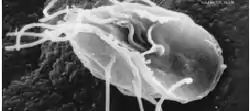

Parásitos

La mayoría de los parásitos alimentarios son zoonósicos.

- Giardia lamblia